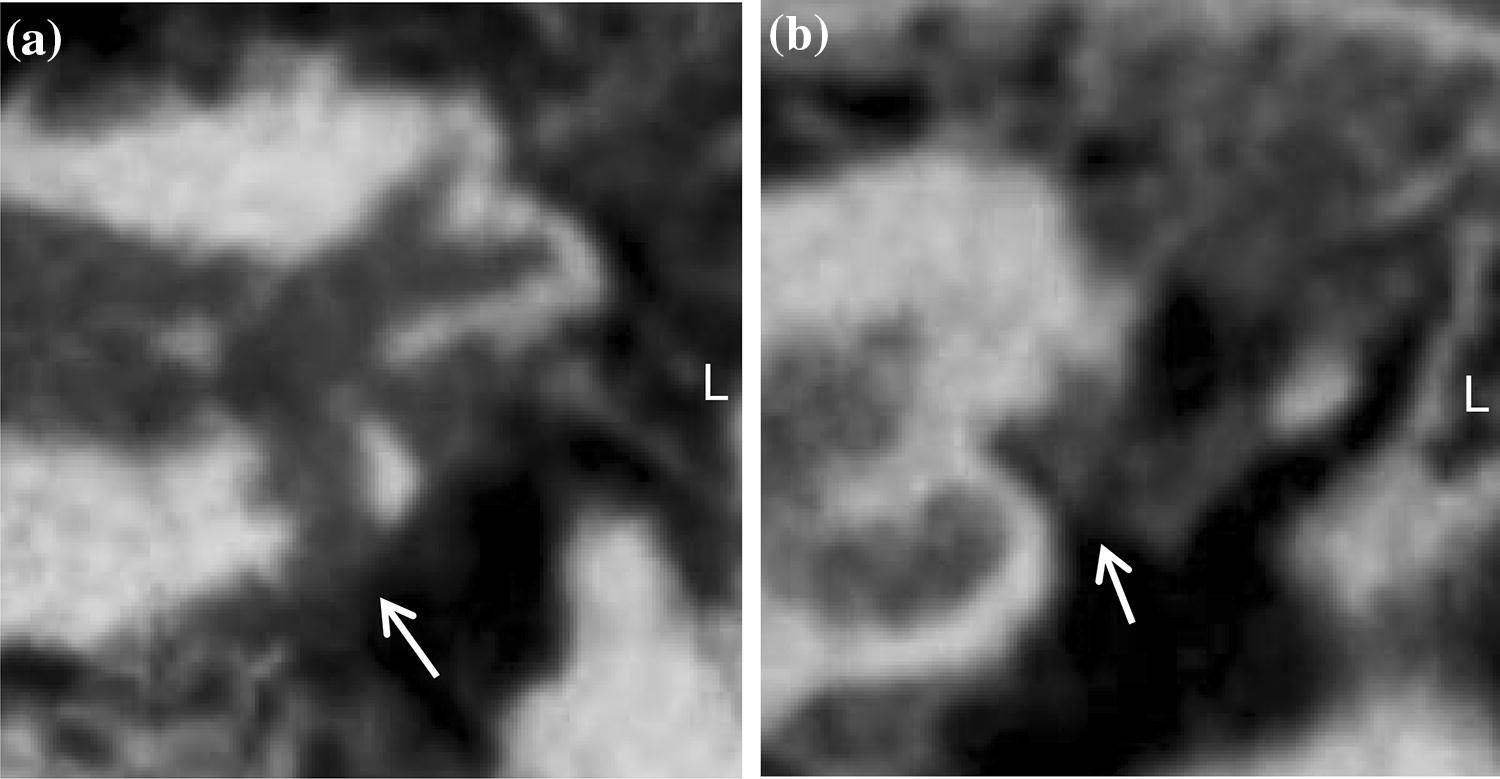

Bony overhangs at the RWN were clearly visualized in seven cases (26%, Fig. 3). Granulation tissue inside the RWN, not allowing to identify the round window membrane (RWM), was found in four cases (15%, Fig. 4a). In all other 23 cases (85%) the RWM was clearly visible. Additional soft tissue inside the oval window niche was seen in four cases (15%, Fig. 4b). In one case (4%) it was possible to describe an additional, secondary RWM (Fig. 5). Regarding these 108 radiologically ‘tiny’ items the neuro-radiologist was not able to make a clear decision in nine cases (8%).

Fig. 4

Coronal view of a left temporal bone in CBCT imaging. The RWN (a) and the OWN (b) are completely opacified ( →). The soft tissue extents to the ossicular chain in (b)